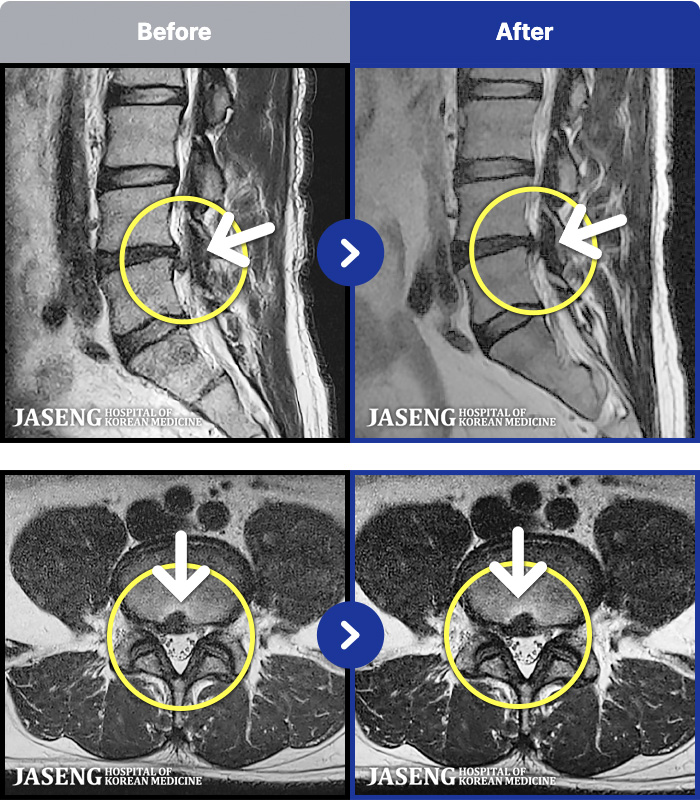

MRI ġ

1,301 MRI ũ ʸ Ȯϼ.